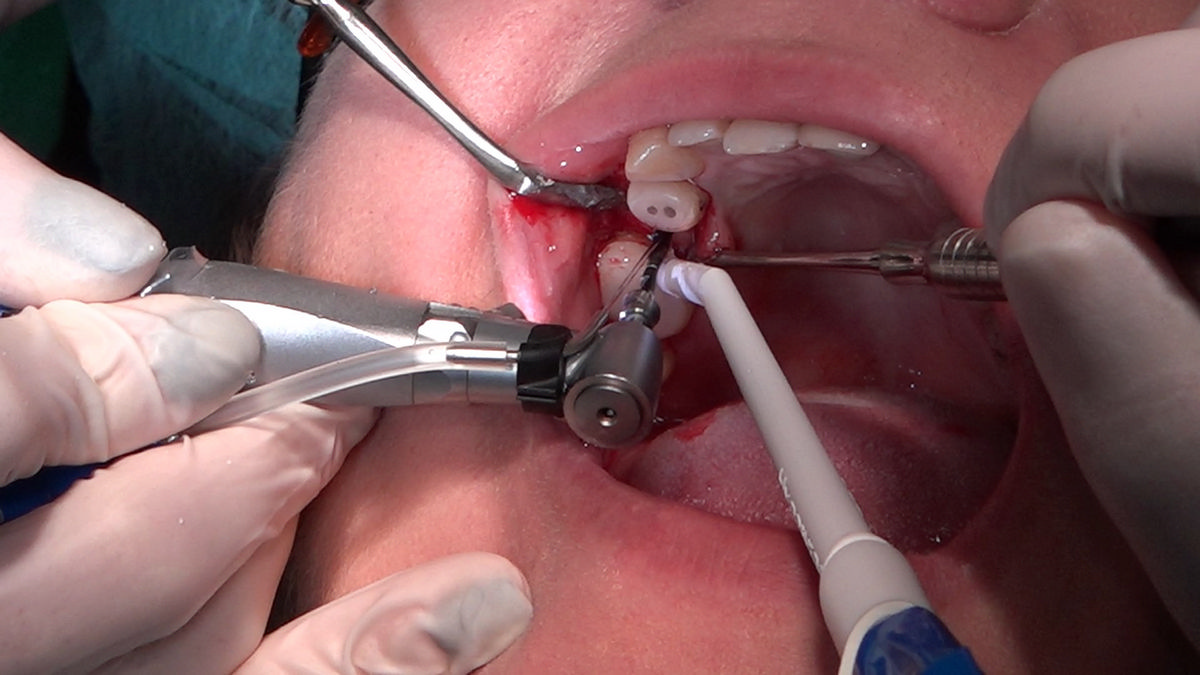

PRACTICULUM IMPLANTOLOGII - SEZON X - SESJA 4 - GRUPA B